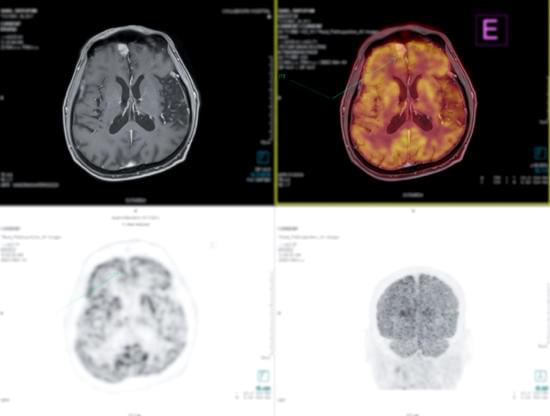

양전자 방출 단층촬영(PET) 스캔에 대한 이해

양전자 방출 단층촬영(PET) 스캔은 의료 이미징 기술로, 환자의 신체 특정 부위에 대한 상세한 이미지를 제공하며 주로 암, 심장 질환, 그리고 뇌 장애의 진단과 치료 계획 수립에 활용됩니다.

뇌 장애의 진단: 알츠하이머 병 같은 신경 퇴행성 질환의 조기 진단에 유용합니다. 뇌의 대사 활동을 시각화하여, 정상적인 뇌와 비교하여 활동 감소 지역을 식별할 수 있습니다.

스캔 수행: 환자는 PET 스캔 기계 내에 위치하고, 기계는 몸 전체 혹은 특정 부위의 상세 이미지를 촬영합니다.

이미지 분석: 방출된 감마선을 검출하여 컴퓨터가 이미지를 생성하고, 의사가 이를 분석합니다.